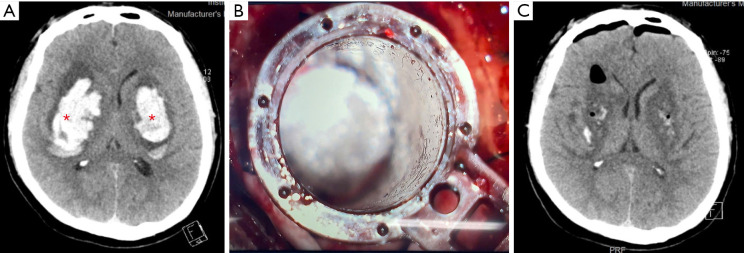

Case description: A 44-year-old male, previously independent in daily activities with a medical history of hypertension, presented to the emergency department with severely altered consciousness [Glasgow Coma Scale (GCS) score 6]. Immediate intubation and admission to the intensive care unit (ICU) were initiated. Computed tomography (CT) angiography confirmed no evidence of vascular abnormalities or aneurysms. Tubular retractor-assisted microsurgical evacuation was performed to remove the hematoma and reduce intracranial pressure (ICP). The patient demonstrated neurological improvement, including spontaneous eye opening by postoperative day 3 and discharge from the ICU on day 10, highlighting the effectiveness of the intervention. He was subsequently discharged from the hospital on day 15 and transferred to a rehabilitation center for further recovery. Bilateral basal ganglia hemorrhage is rare, and its management often poses challenges due to high morbidity and mortality rates.

Conclusions: This case underscores the importance of prompt diagnosis and intervention in bilateral basal ganglia hemorrhage. MIS offers a viable therapeutic option that may enhance recovery while reducing surgical risks.